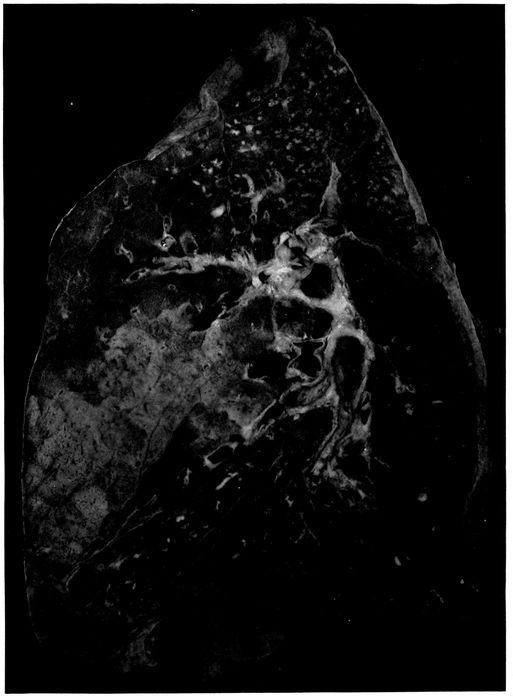

8. Streptococcus pneumonia with massive necrosis 201

9. Abscess below pleura with perforation caused by hemolytic streptococci 202

26. Unresolved bronchopneumonia with tubercle-like nodules of peribronchiolar consolidation best seen in lower lobe; bronchiectasis 268

27. Unresolved pneumonia with peribronchial formation of fibrous tissue; bronchiectasis 270

28. Unresolved pneumonia with bronchiectasis showing new formation of fibrous tissue about a greatly dilated bronchus of which the epithelial lining has been lost 271